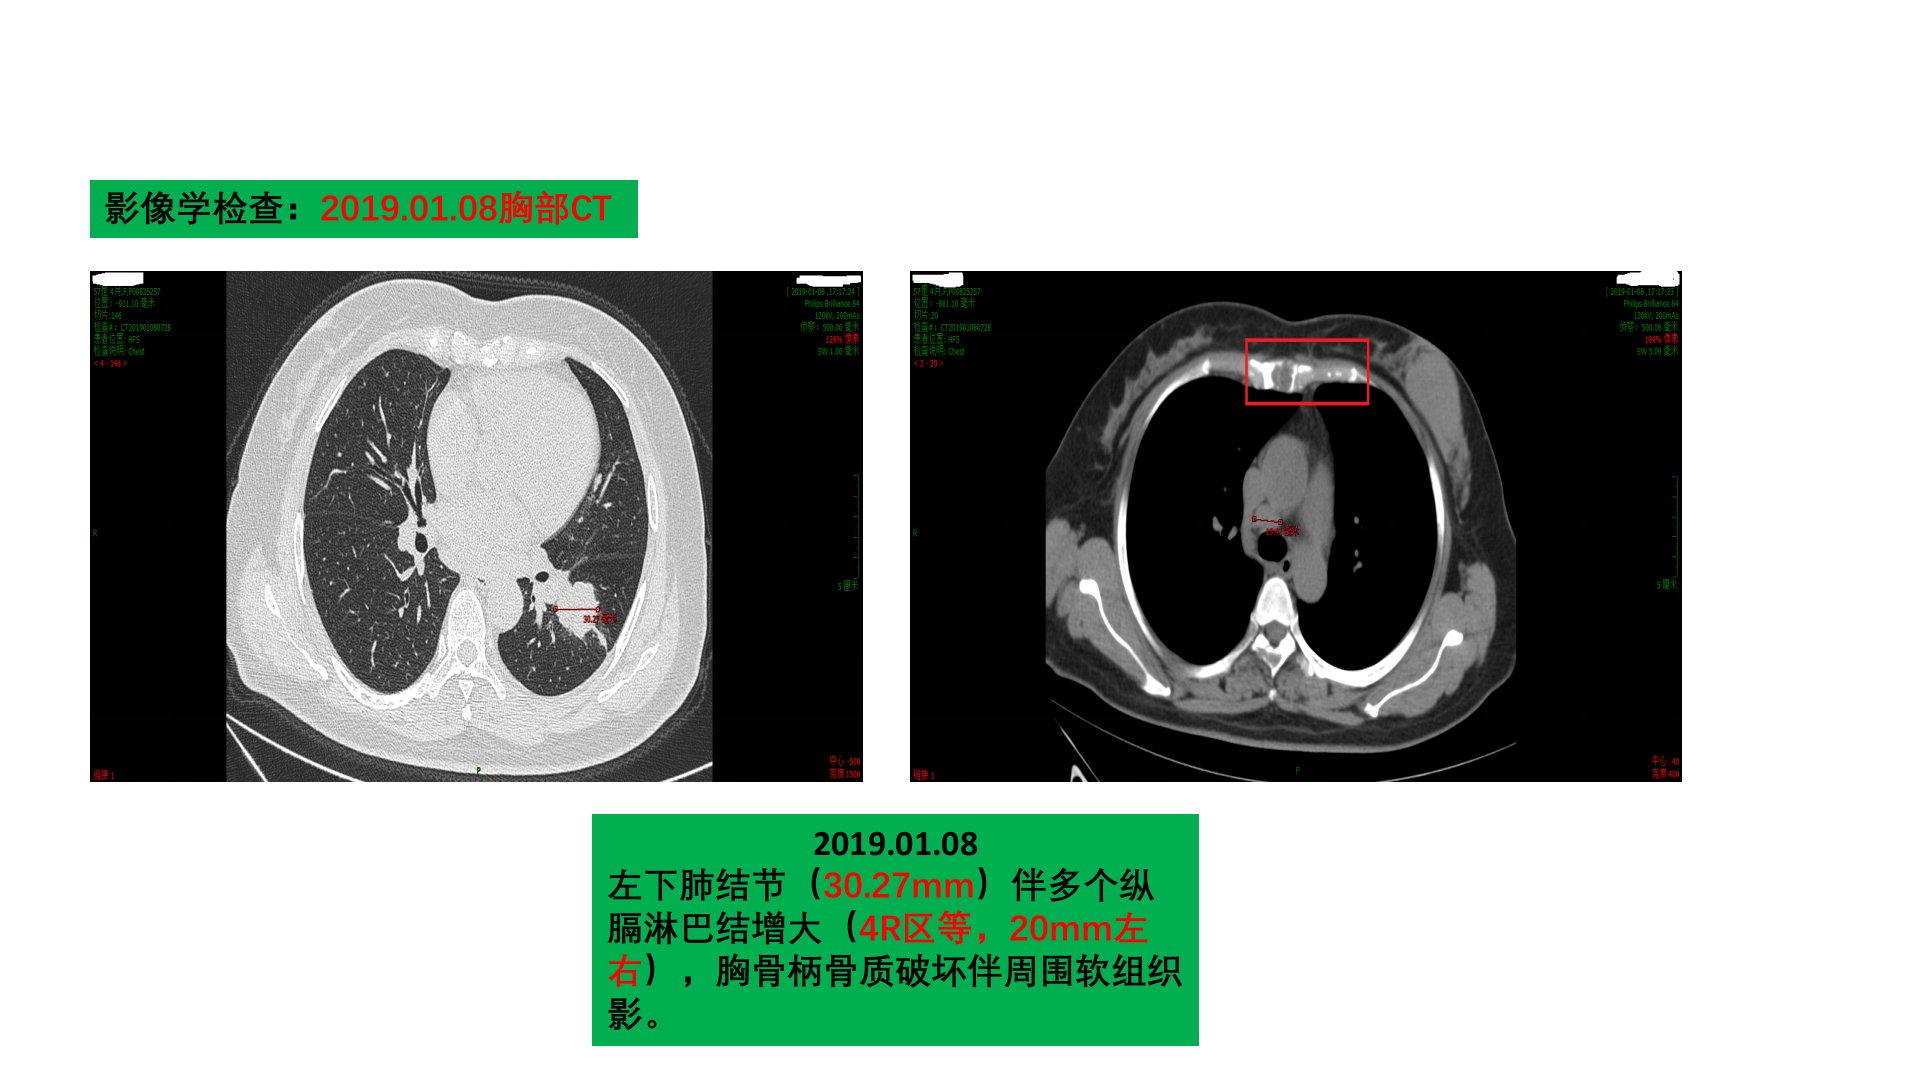

患者吴某某58岁女性2019年1月因胸背部疼痛不适入我院门诊就诊胸部CT提示左下肺结节伴纵膈淋巴结增大胸骨柄骨质破坏。后住院诊疗脑部MRI增强、腹部CT增强等检查未见异常但骨扫描显示多处骨质代谢异常活跃考虑肿瘤骨转移。病理学检查确诊为左下肺腺癌EGFR基因19号外显子缺失突变ALK、ROS1等融合基因野生型诊断为左肺下叶腺癌IVB期。2019年2月开始用吉非替尼和双膦酸盐治疗2019年8月病情出现进展新发多处病灶。参考NEJ009研究调整治疗方案行3周期培美曲塞单药化疗。2020年4月患者因头晕再次入院检查发现脑部和胸部病情进展且出现EGFR基因T790M耐药突变于是采用阿美替尼治疗并进行了全脑放疗后辅以贝伐珠单抗单药治疗。对于EGFR阳性人群一线治疗方案多样临床医生应根据实际情况优化一线治疗综合多种方案和手段使患者总生存期获益。